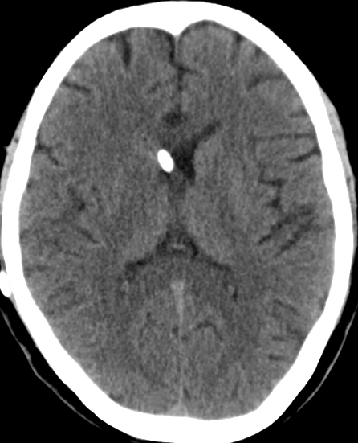

2013-8-2 CT

腰穿脑压240